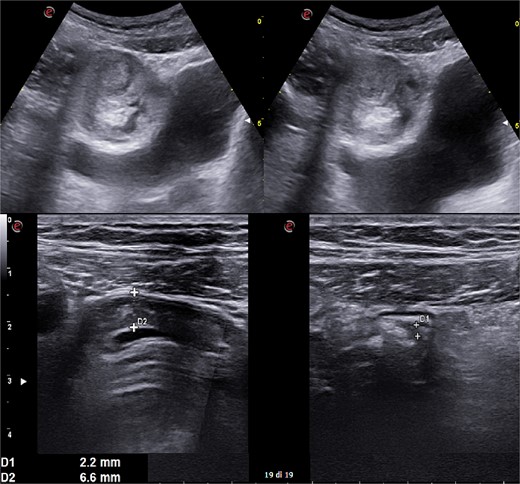

A 31-year-old male was complaining episodes of abdominal pain in the umbilical region with nausea. In medical history he underwent an appendectomy. Chronic gastritis was found on esophagogastroduodenoscopy (EGD) and proton-pump inhibitors (PPI) treatment was started, with regression of symptoms. After two months, he took ketoprofen for back pain for two days when a severe abdominal pain in the umbilical and right iliac region started, with nausea and vomit. He had normal vital signs and tenderness in the right lumbar and iliac regions. Blood exams showed leucocytosis (GB 14.120 × 106/ml) with neutrophilia (88%). A plain abdomen X-ray showed absence of representation in the right regions, with small bowel loops’ distension on the left (Fig. 1). An abdomen US displayed the presence of visceral distension with cockade appearance, consistent with an inflammatory condition of the cecum and the ileocecal site, with wall thickening of 6 up to 10 mm and free fluid near the cecum (Fig. 2). Contrast-enhanced CT confirmed wall thickening of the last ileal loop and the cecum up to 20 mm (Fig. 3A and B). Antibiotic therapy was started. The next day the pain worsened and there was an abdominal mass in the right iliac region with rebound tenderness. Blood examination showed further increase in leucocytosis (GB 18560) and a new CT was done. The wall thickening increased up to 24 mm, and the last ileal loop was more hypointense, with a twisted appearance around its mesentery (Fig. 3C). Exploratory laparotomy was performed. During surgery we found an ileal intussusception of the distal ileum near the cecum, and an ileocecal resection with ileo-colic anastomosis was done. On the first post-operatory day he developed haematochezia and acute anaemia, so he underwent reintervention with resection of the anastomosis and ileostomy. The following post-operative course was uneventful.

Plain abdomen X-ray showing limited visibility of the colon on the right side with small bowel loops’ distension on the left regions, without free air.